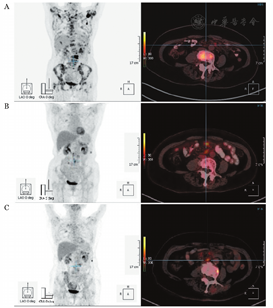

患者治疗过程中观察结果见表1。细胞因子释放综合征(CRS):Ⅱ级,不良反应轻微可耐受。治疗后60 d,患者腹痛症状逐渐消失、病情稳定。复查PET-CT:L1-5水平肠系膜密度不均匀增高灶,边缘模糊,SUVmax 6.36,较前范围缩小。随访至CAR-T19细胞治疗后150 d,患者病情稳定,外周血PD-1阳性表达率0.68%,CAR-T19细胞阳性表达率0.06%,仍在进一步观察中。患者初诊、化疗后及CAR-T19细胞治疗后PET-CT检查结果见图1。

患者,女,70岁,因"低热、腰痛、乏力10 d"于2017年7月就诊。骨髓活检病理示小B细胞淋巴瘤侵犯骨髓。FISH检测示IgH-BCL2阳性率4.8%。MYD88基因检测阴性。PET-CT:多发骨质密度不均匀,部分骨质破坏,代谢异常增高(L3椎体局部SUVmax=28.20);颈部双侧、右侧锁骨上窝多发增大淋巴结,代谢异常增高(SUVmax=8.59);L2-3间盘水平腹腔左侧肠系膜区软组织肿块,代谢异常增高(SUVmax=8.57)。临床诊断:滤泡淋巴瘤Ⅳ期B组。予以2个疗程FC(氟达拉滨25 mg/m2×3 d+环磷酰胺250 mg/m2×3 d)方案、4个疗程R-CHOP(利妥昔单抗375 mg/m2+环磷酰胺750 mg/m2+表柔比星65 mg/m2+长春地辛3 mg/m2+泼尼松60 mg/m2×5 d)方案化疗;辅以唑来膦酸盐治疗。患者低热、腰痛、乏力缓解,逐渐出现间断腹痛症状。故复查PET-CT:原片所示的多发骨质高代谢灶代谢明显减低;原片颈部双侧及右侧锁骨上窝多发增大淋巴结、L2-3间盘水平腹腔左侧肠系膜区软组织肿块基本消失,代谢较前明显减低;L1-5水平肠系膜密度不均匀增高,范围较前增大,代谢不均匀异常增高(SUVmax=6.70),考虑淋巴瘤浸润。